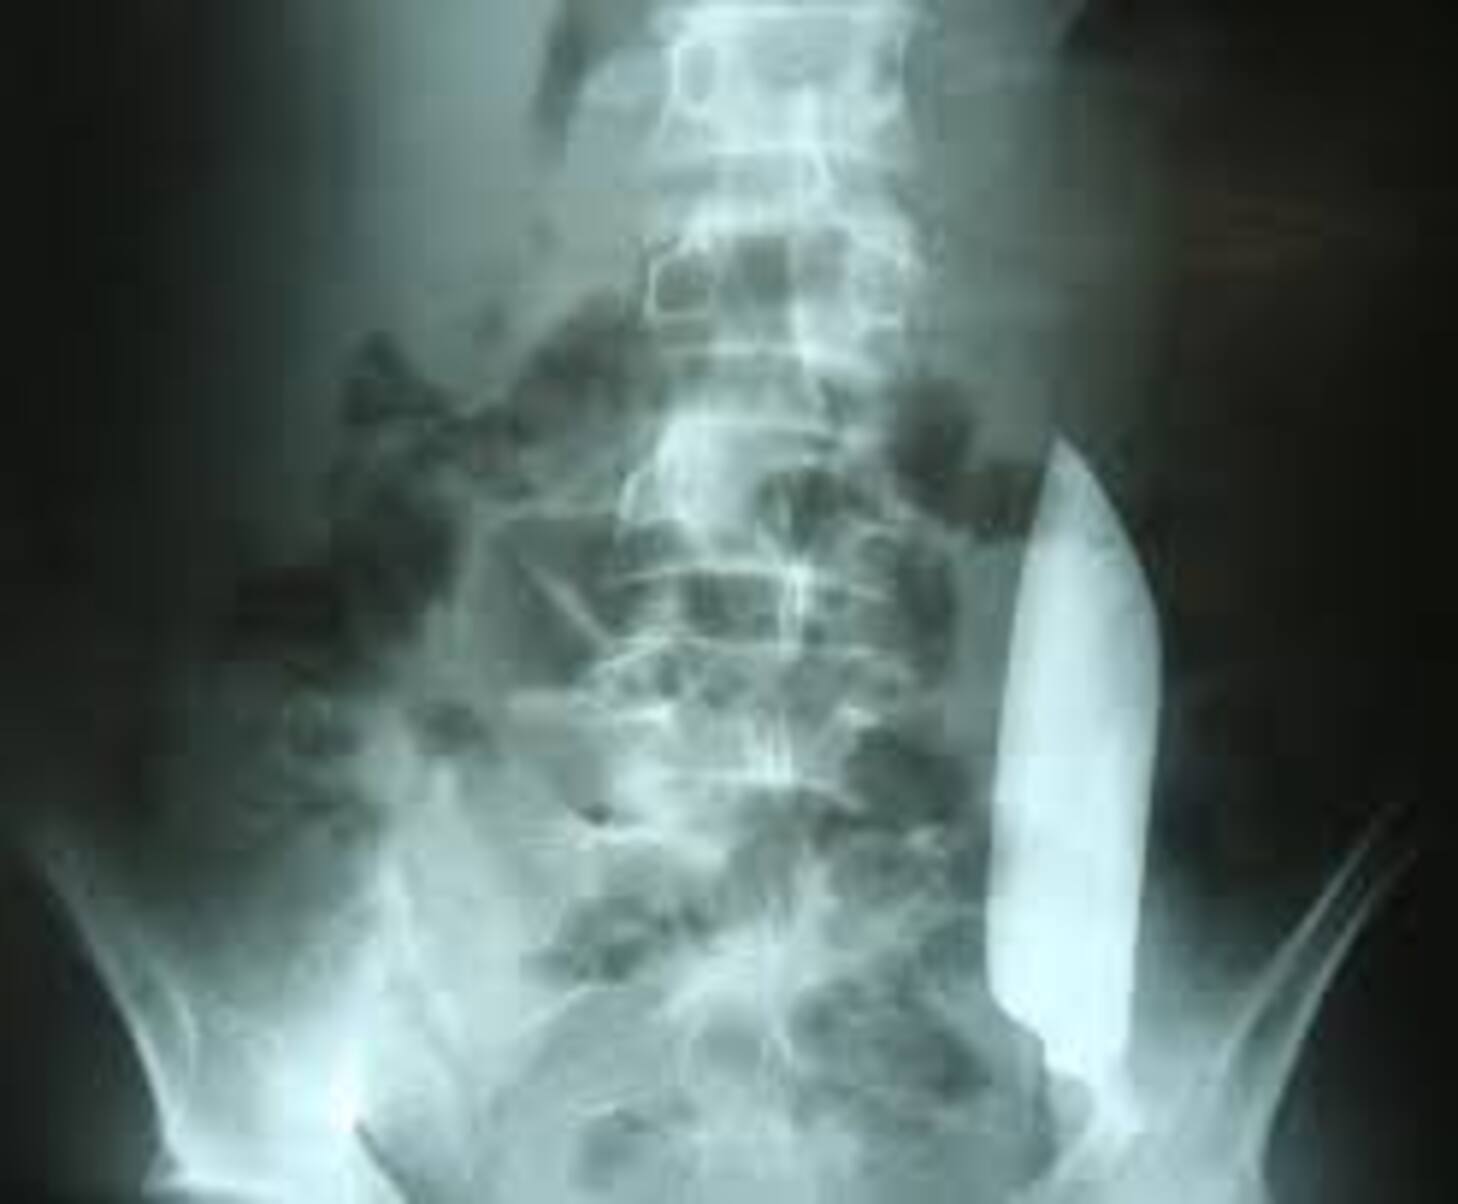

Inquiet, le patient finit par se rendre aux urgences. Les médecins, étonnés par l’absence d’anomalies cliniques, décident de faire une radiographie.

Ce qu’ils découvrent les laisse sans voix :

Une lame métallique longue de 15 cm flottant librement dans l’abdomen.

Pire : elle avait bougé d’un côté à l’autre du petit bassin… sans provoquer de dégâts majeurs.

Hormis une petite coupure d’un centimètre sur la face antérieure du foie – blessure due à l’agression initiale –, aucun organe vital n’a été touché.